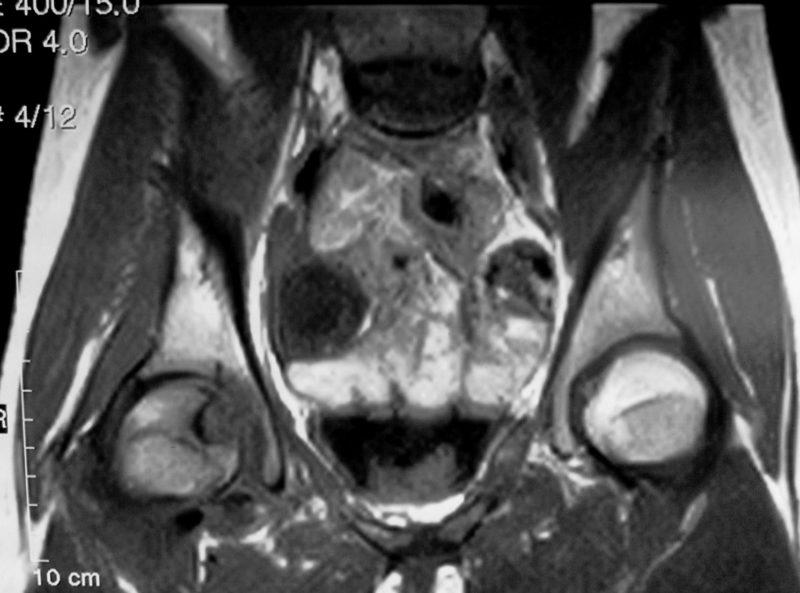

Фото МРТ тазобедренного сустава:

На МРТ помимо костей видны мягкие ткани, но понять что-либо на подобных снимках под силу только специалисту